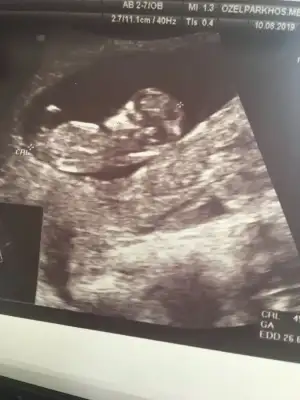

. Sizce bu nedir 11+4Kız bu bebiş.nub çizgisi paralel

Kız bence canım. Sizce bu nedir 11+4 ☺

Kız canım bu bebiş. Sizce bu nedir 11+4 ☺

Hadi inşallah banada öyle geldi amaKız bence canım![]()

11+4 göre erkek gibi diyorum. Sizce bu nedir 11+4![]()